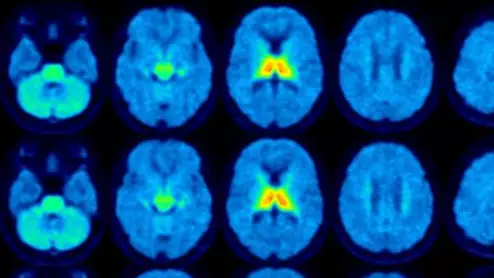

molecular imaging study on brain connections in obese individuals

New research, presented at SNMMI 2023, details how the brains of obese individuals differ from those who maintain a healthy weight.